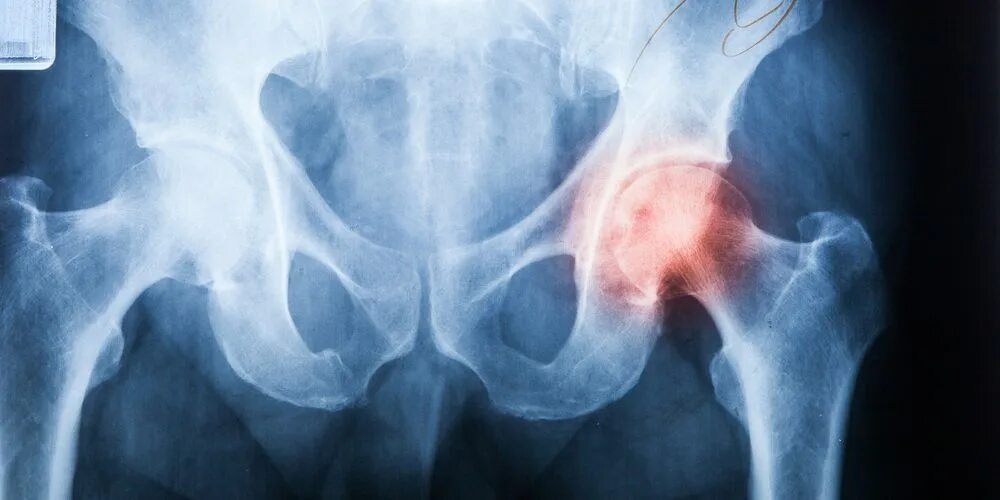

Аваскулярный некроз тазобедренного сустава